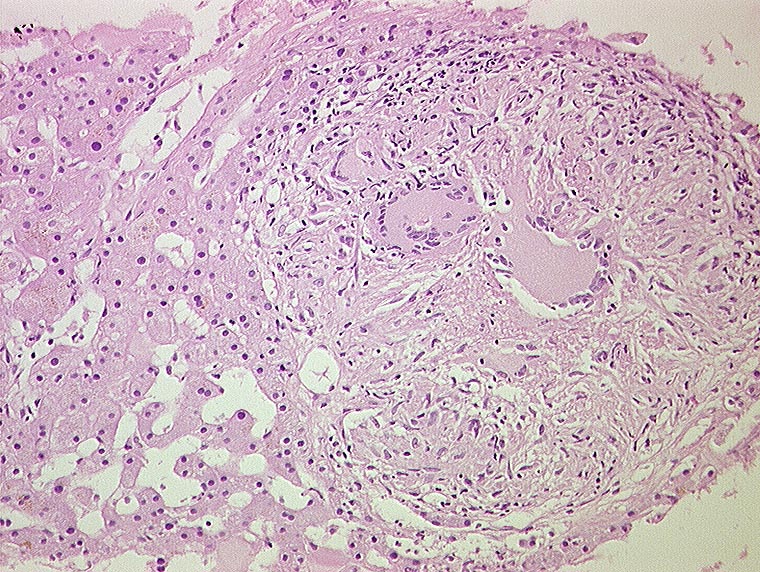

Miliartuberkulose : produktives Granulom

Entzündung infektiös

Leber

Nicht verkäsendes produktives Granulom aus Epitheloidzellen und Langhans'schen Riesenzellen mit hufeisenförmig angeordneten Kernen.